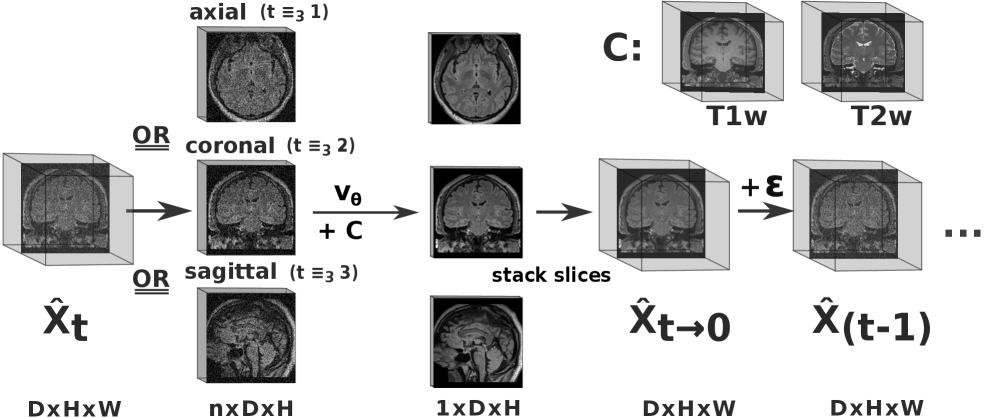

3.2.1 2.5D diffusion

Operating the neural denoiser on full-resolution 3D images is unfeasible on current hardware due to memory constraints. Thus, we perform a 2.5D diffusion approach (Fig. 2): We define the diffusion process in 3D, i.e. the latent diffusion images are volumes . The 2.5D denoiser ingests 2D slabs with , as inputs and predicts slices . implicitly stacks these slices to form the predicted noise-free volume . Based on this, we include the following 2.5D components:

multi-slice inputs

predicts a single slice from a slab formed with the two bi-directional adjacent slices (i.e. 5 in total) of both, the conditioning and the diffusion latent . This allows for a harmonization of image appearance and feature creation across slices during the sampling process.

orthogonal denoising

We rotate the slicing views (sagittal, coronal, axial) between denoising steps to improve 3D information transfer and combat slicing artifacts (Fig. 2). For simplicity and to avoid extra training effort, all views are predicted by a single network. Note that YODA’s 2.5D sampling scheme does not increase the required due to multi-plane averages or correction steps [61, 35].